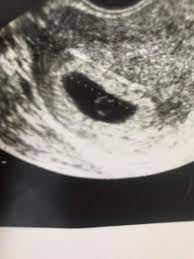

4 ssw ultraschall fruchthöhle. SSW Fruchthöhle Dottersack aber kein Embryo. Hier sieht man deutlich die schwarze Fruchthöhle der Embryo lässt sich noch nicht erkennen. Dies dient als ersten Anhaltspunkt für das Alter deiner Schwangerschaft.

Nur Fruchthöhle zu sehen bei 70 SSW.

Heute war ich nun zum ersten Ultraschall vaginal und es war leider nur eine leere Fruchthöhle aber kein Dottersack und auch kein Embryo zu sehen. Eine Schwangerschaft an 45 SSW. Frauenarzt Termin laut Ultraschall bin ich ssw 55 wobei allerdings nur eine leere fruchthöhle zu sehen war von 095cm. Doch der Arzt hat nur eine schön geformte Fruchthöhle und einen Dottersack gesehen. Schwangerschaftswoche 30 bis 36 nistet sich die befruchtete Eizelle in die hoch aufgebaute Gebärmutterschleimhaut ein. Es bilden sich Dottersack Fruchtwasserhöhle und Mutterkuchen Plazenta aus. Aber lässt sich auf dem Ultraschall in der 4.